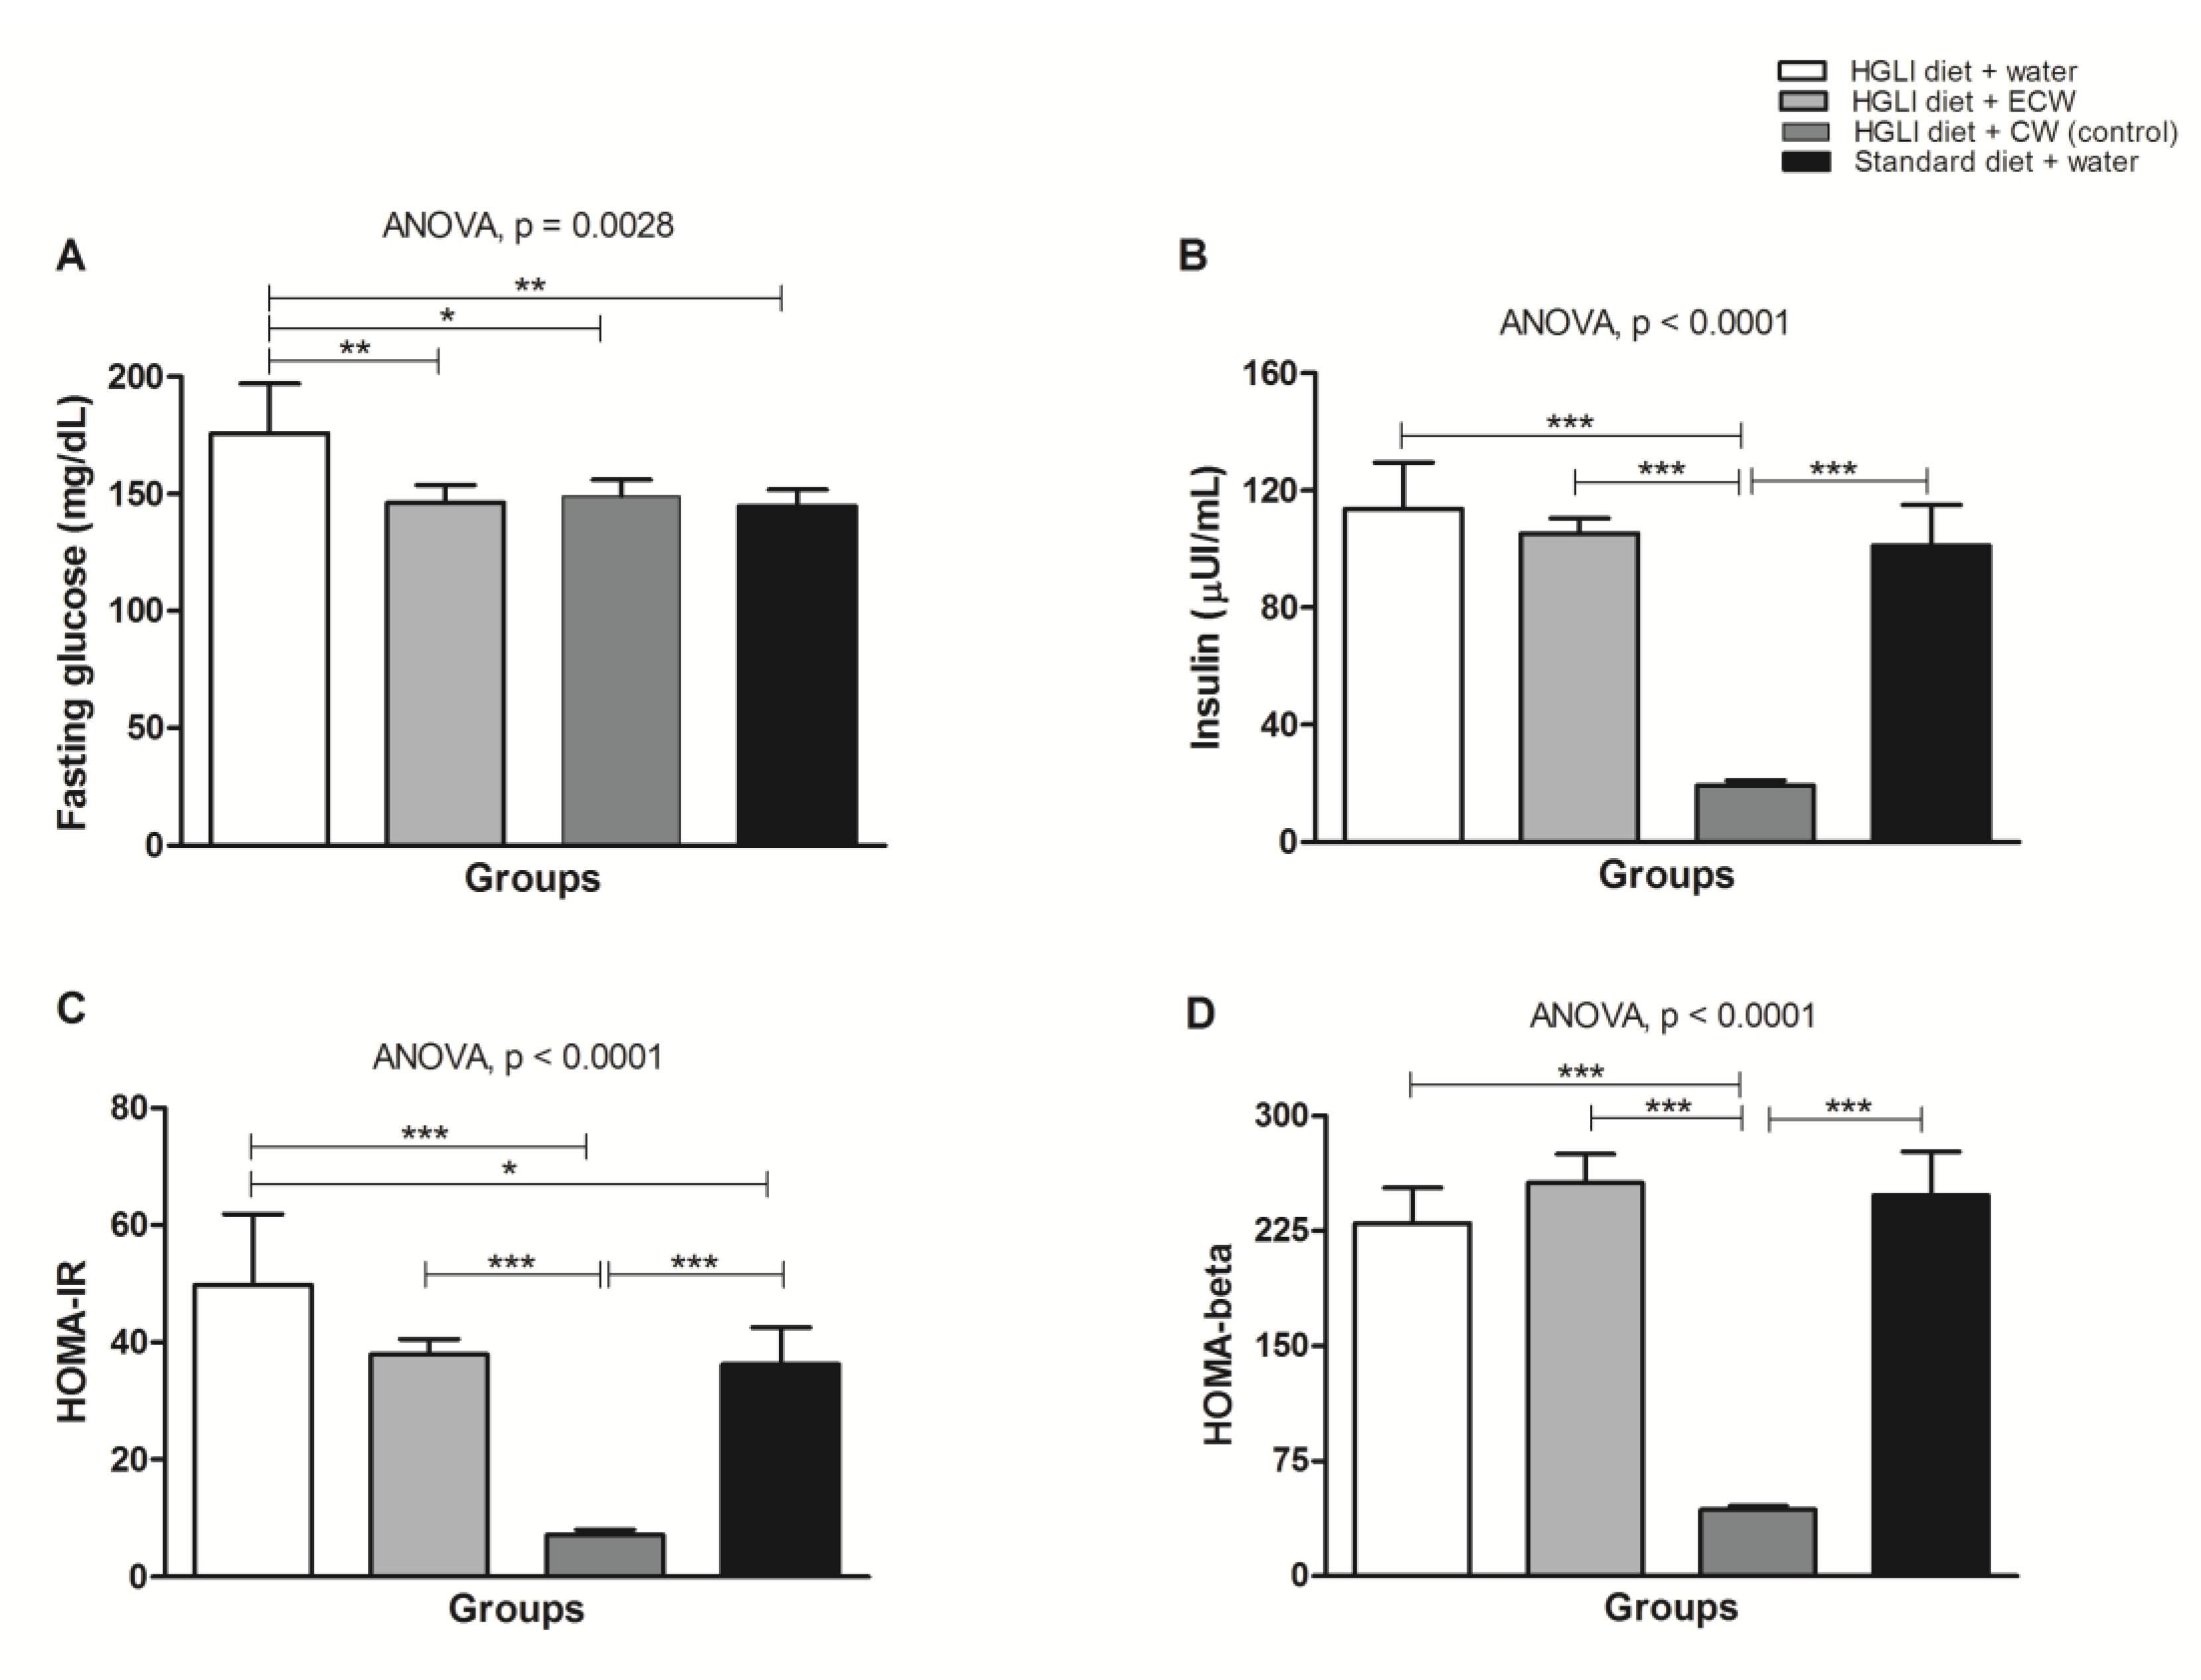

3.5. Evaluation of In Vivo Biochemical Parameters

3.6. Pancreas Histopathology of Wistar Rats